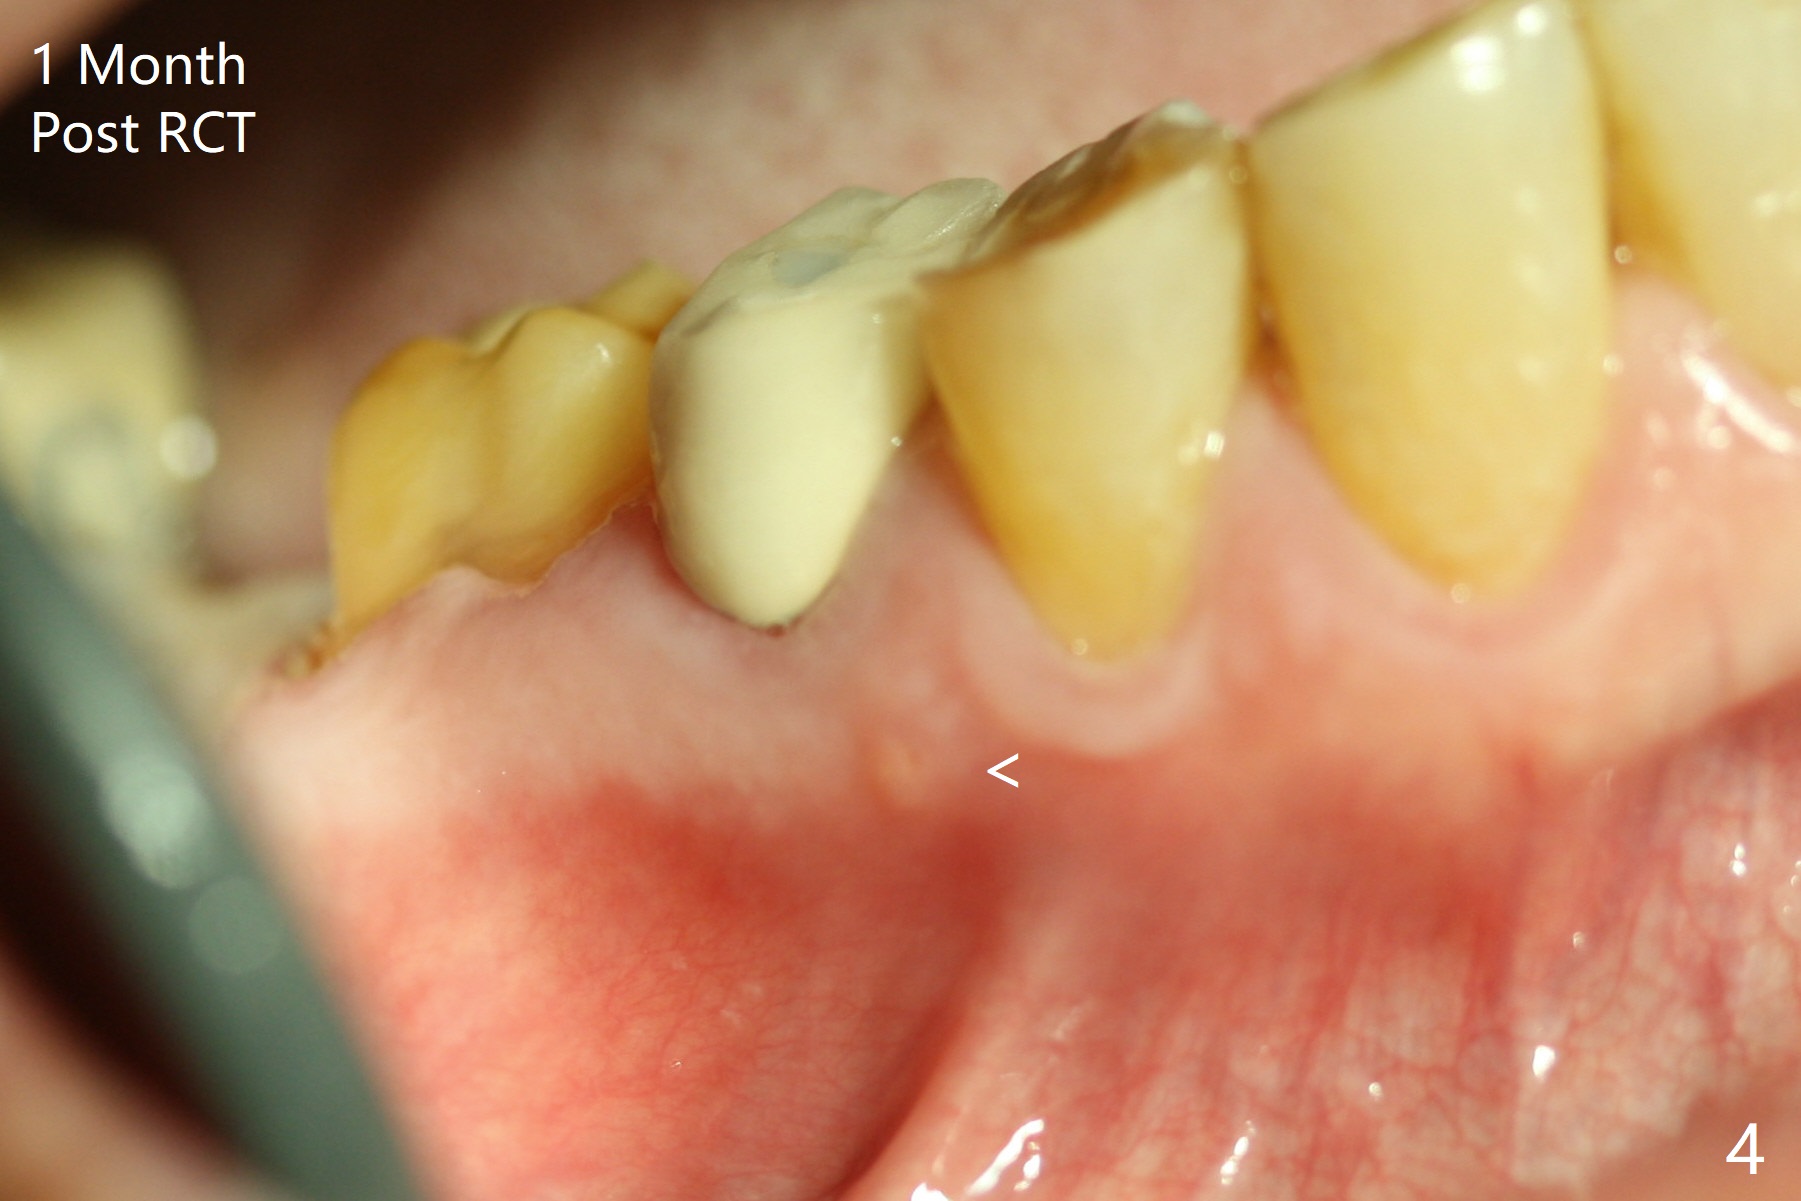

While the guided implant at #19 is osteointegrating, porcelain chips in the mesial marginal ridge of the retainer at #30 (Fig.2 *), causing food impaction between #29 and 30. The units #30 and 31 are removed. Impression is taken for guide at #31 (Fig.1). A temporary crown is fabricated for #30. Since there is sufficient bone, a 5x11.5 mm implant will be placed (Fig.1). If mouth opening is limited, a 10 mm long will be used. RCT will be done for the tooth #29 first for the buccal fistula (Fig.2). The fistula disappears 1 month post RCT (Fig.3,4 <) when a 5x10 mm implant is placed at #31.